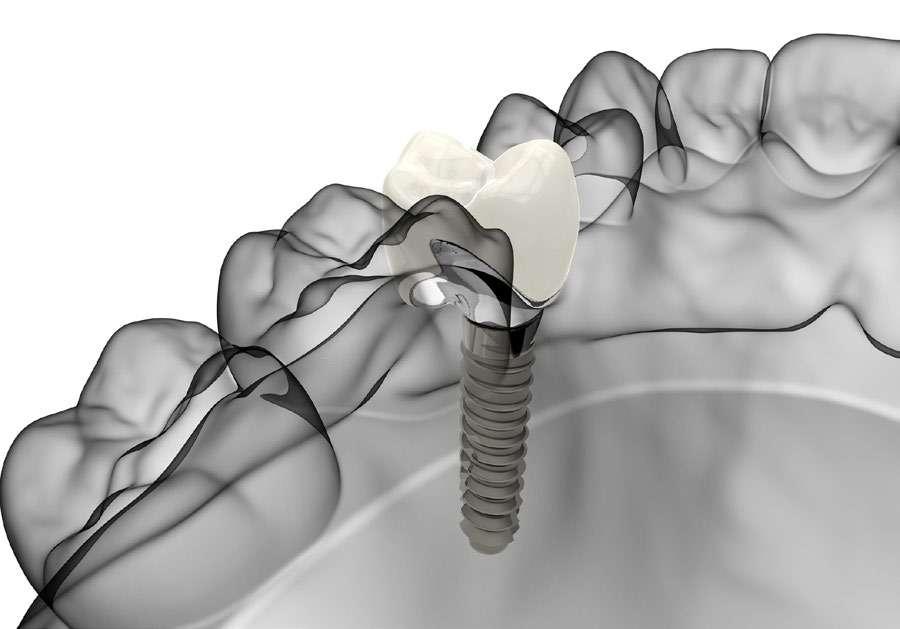

Figuras 3-6. Imágenes de un caso de prótesis atornillada en molar unitario inferior. Vemos el estado de los tejidos blandos gingivales tras la segunda fase y colocación del transepitelial unitario y la radiografía. En las imágenes inferiores (5 y 6) observamos el caso a los 4 años y 10 años de seguimiento, con estabilidad completa de los tejidos óseos peri-implantarios.

Figuras 7-10. En las dos imágenes superiores (7 y 8) observamos la realización de la prótesis cementada mediante un bioplilar fresado a la altura gingival con la radiografía antes del cementado de la corona. En las imágenes inferiores (9 y 10) vemos la prótesis a los 7 años de seguimiento y a los 9 años transformada en una prótesis atornillada al perderse la pieza anterior al implante y realizarse un puente con el nuevo implante. En este caso, el nivel óseo permanece estable con el paso del tiempo.